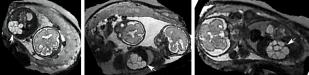

Evaluation of Adult Brain MRI Reconstruction: We evaluate the performance and limitations of PVR in terms of accuracy and robustness with synthetic non-rigid deformations of adult brain data. Similar to [24], an isotropic T2-weighted adult brain phantom with no noise obtained from the Brainweb database [34] is used for this experiment. Synthetic non-rigid motion artifacts are generated by skewing (shearing) the original image using:

where we use one combined skewing value in the -direction defined by . After that a motion-corrupted 3D stack is constructed by sampling 2D images from both skewed and motion-free stacks in an interleaved manner similar to fetal MRI acquisition [35]. Three stacks are used for the reconstructions where each stack is sampled with a voxel size of xx . We use standard axial, sagittal, and coronal orientations as shown in Fig. 9. An HR image with isotropic voxel size is reconstructed using SVR [17], square patch- and superpixel-based PVR.

Reconstruction of Adult Brain MRI: Experiments on adult brain MR data using the Brainweb database [34] included introducing synthetic non-rigid motion artifacts as described in Sec. IV. Example slices of standard planes of original and corrupted data are depicted in Fig. 9. Comparative experimental results of SVR and PVR reconstruction methods are shown in Fig. 10 for PSNR, SSIM and CC. For all metrics, PVR shows an improved performance over SVR, particularly in presence of deformations with higher skewing angles. Further, we observe that superpixel-based PVR achieves similar performance as PVR using arbitrary square patches, while requiring a lower amount of input patches.